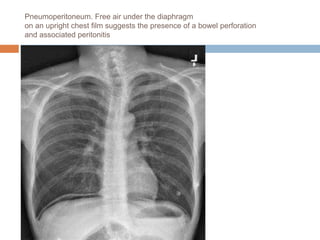

Pneumoperitoneum. Free air under the diaphragm

on an upright chest film suggests the presence of a bowel perforation

and associated peritonitis